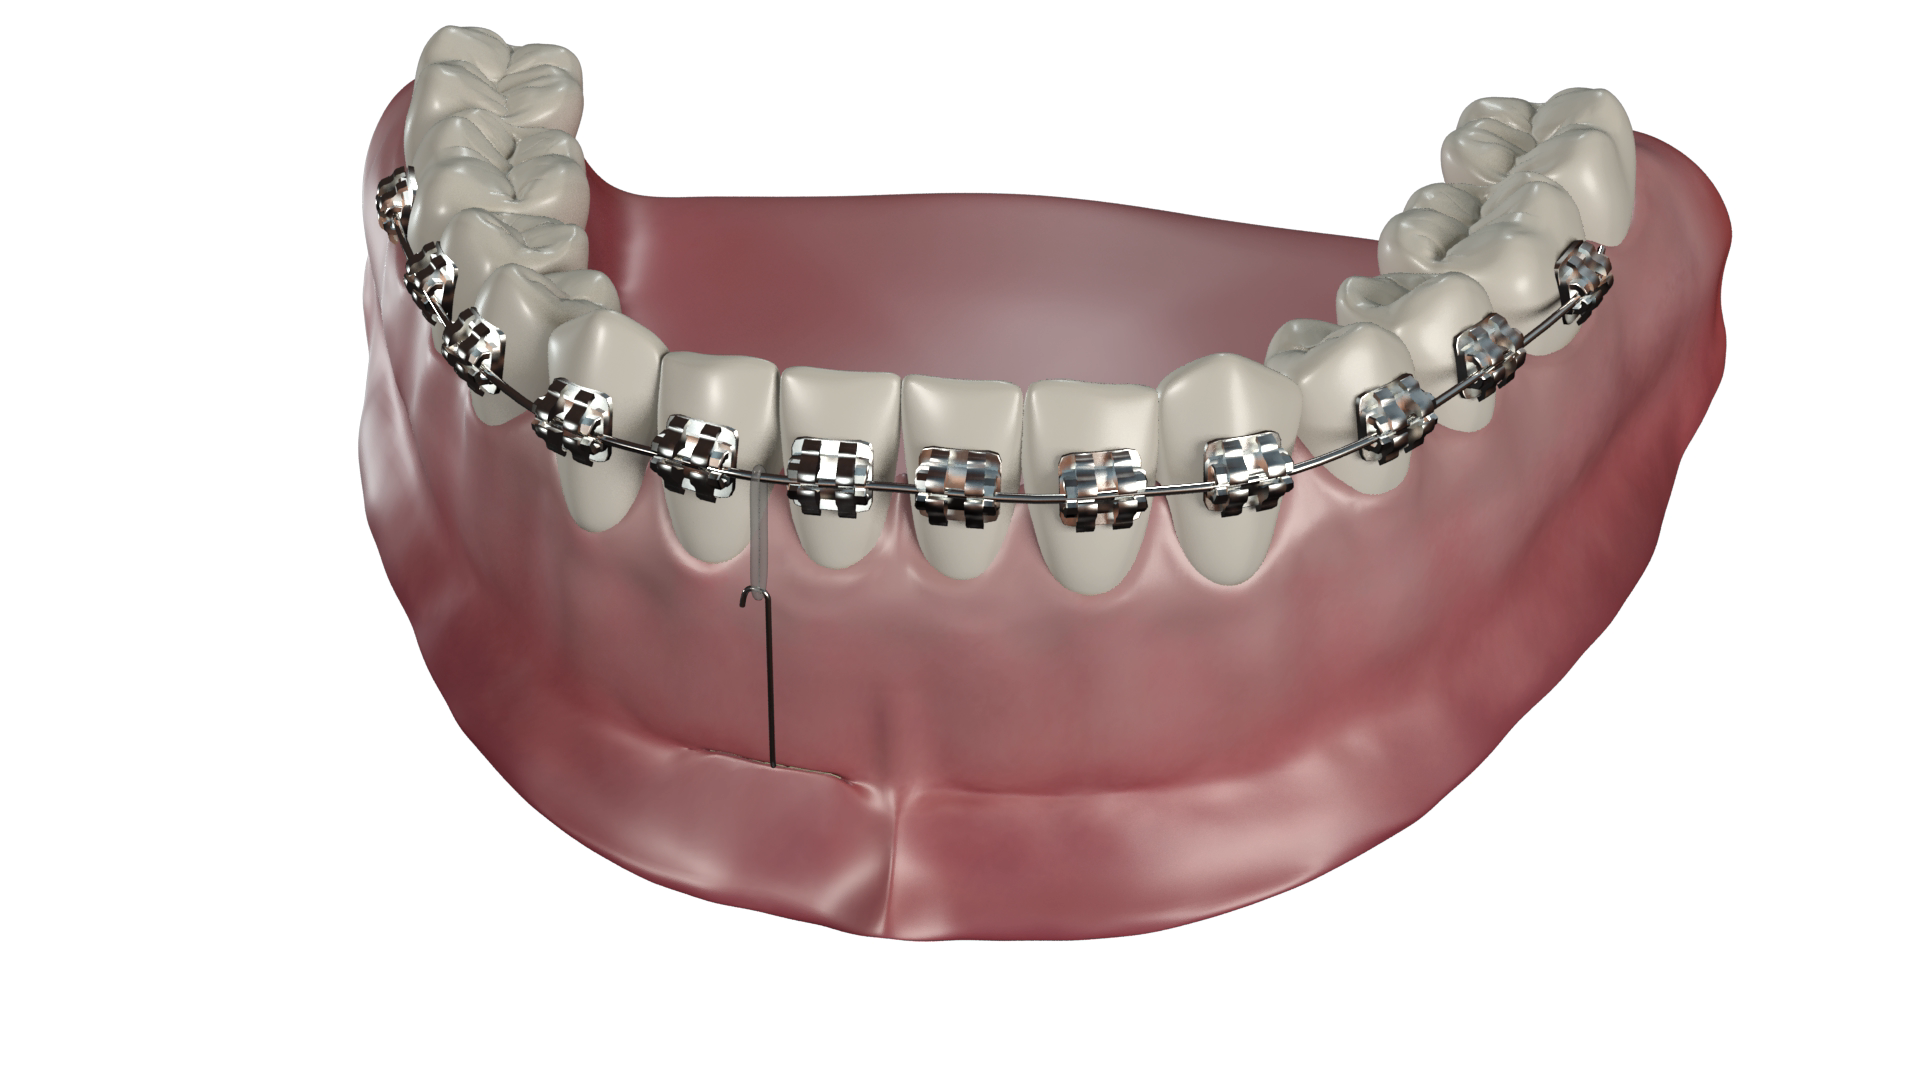

- une ou deux micro-vis en alliage de titane TiAl6V4, autoforeuse et autopréhensible sur le tournevis dédié, enfouie en fond de vestibule au-delà des apex

- une connectique en alliage CTnox spécialement conçu et développé pour le système CT8, attachée à la vis et émergeant au centre du vestibule dans une muqueuse non kératinisée. Le fil est plaquée contre la corticale osseuse sous la muqueuse et au delà il longe la gencive ce qui en fait un dispositif très discret et faiblement invasif pour le patient.

- Vissage de la ou des vis et plaquage du fil contre la corticale osseuse

Le geste peut être réalisé quasiment en aveugle car il n’y a aucun risque anatomique pour les structures sous-jacentes.

Le bras de la connectique est libéré de l’encoche du tournevis par un simple mouvement de doigt dès que la vis commence être vissée dans la corticale.

Le vissage est réalisé jusqu'à ce que la vis paraisse entraîner la connectique dans sa rotation. Elle est alors légèrement desserrée pour permettre de la repositionner avant son serrage final.

- Réalisation d'une baïonnette au niveau du trait d'incision (fond de vestibule)

En deçà, le fil est plaqué contre l’os, au-delà il doit longer la gencive sans appui.

Elle est réalisée à l’aide de l’instrument dédié dont la gorge coiffe le fil et qui est tourné d’ un huitième à un quart de tour environ afin de compenser l’épaisseur de muqueuse.

Cette manoeuvre apparaît à l’usage la plus délicate à réaliser de toute la procédure de mise en place d’un CT8 car un fil trop écarté gênera à la longue la muqueuse labiale ou jugale, alors qu’un fil trop serré comprimera la gencive d’une manière excessive.

- Mise en forme du fil

Il longe la surface muqueuse sans la comprimer depuis le fond du vestibule, puis est façonné en ressort ou simplement replié en crochet pour pouvoir être relié à l’appareil ou directement aux les dents à déplacer.